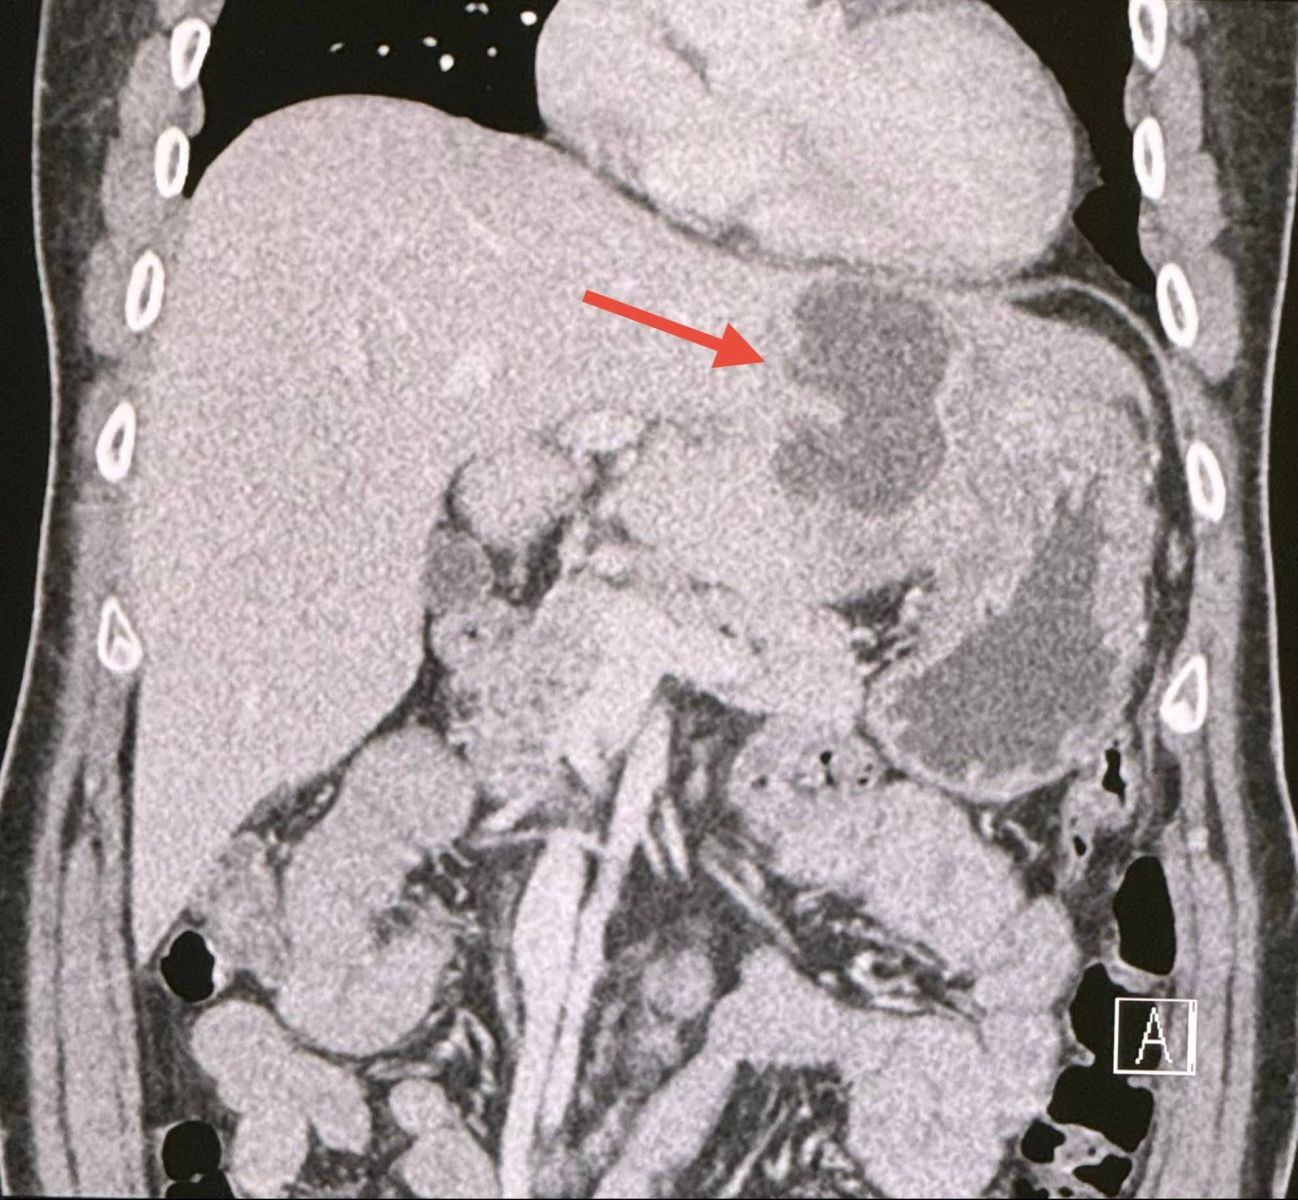

เจาะเลือด เม็ดเลือดขาวในเลือดสูง 15,050 ค่า alkaline phosphatase สูง 564 ส่งเลือดเพาะเชื้อ ไม่ขึ้นเชื้อแบคทีเรีย ทำอัลตราซาวด์ช่องท้อง สงสัยฝีในตับข้างซ้ายขนาด 5.2 × 4 เซนติเมตร ทำคอมพิวเตอร์ช่องท้อง เห็นฝีขนาดใหญ่ในตับด้านซ้ายขนาด 6.6 × 4.3 เซนติเมตร (ดูรูป)

วินิจฉัย: ฝีในตับขนาดใหญ่ในคนที่เป็นโรคเบาหวาน